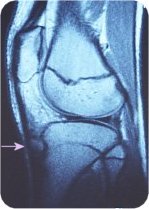

X-rays are the most helpful, which shows changes in the epiphyseal nuclei and free fragments localized to the tibial tuberosity (Photo 2), but they vary in size depending on the stage of disease. Magnetic resonance imaging (MRI) is even more useful in detecting thickening of the patellar tendon over the cartilage and surrounding inflammatory changes (Photo 3). Ultrasound can also show enlarged bones and tendons, as well as new blood vessels. (Photos 4 and 5)

Photo 3 MRI images